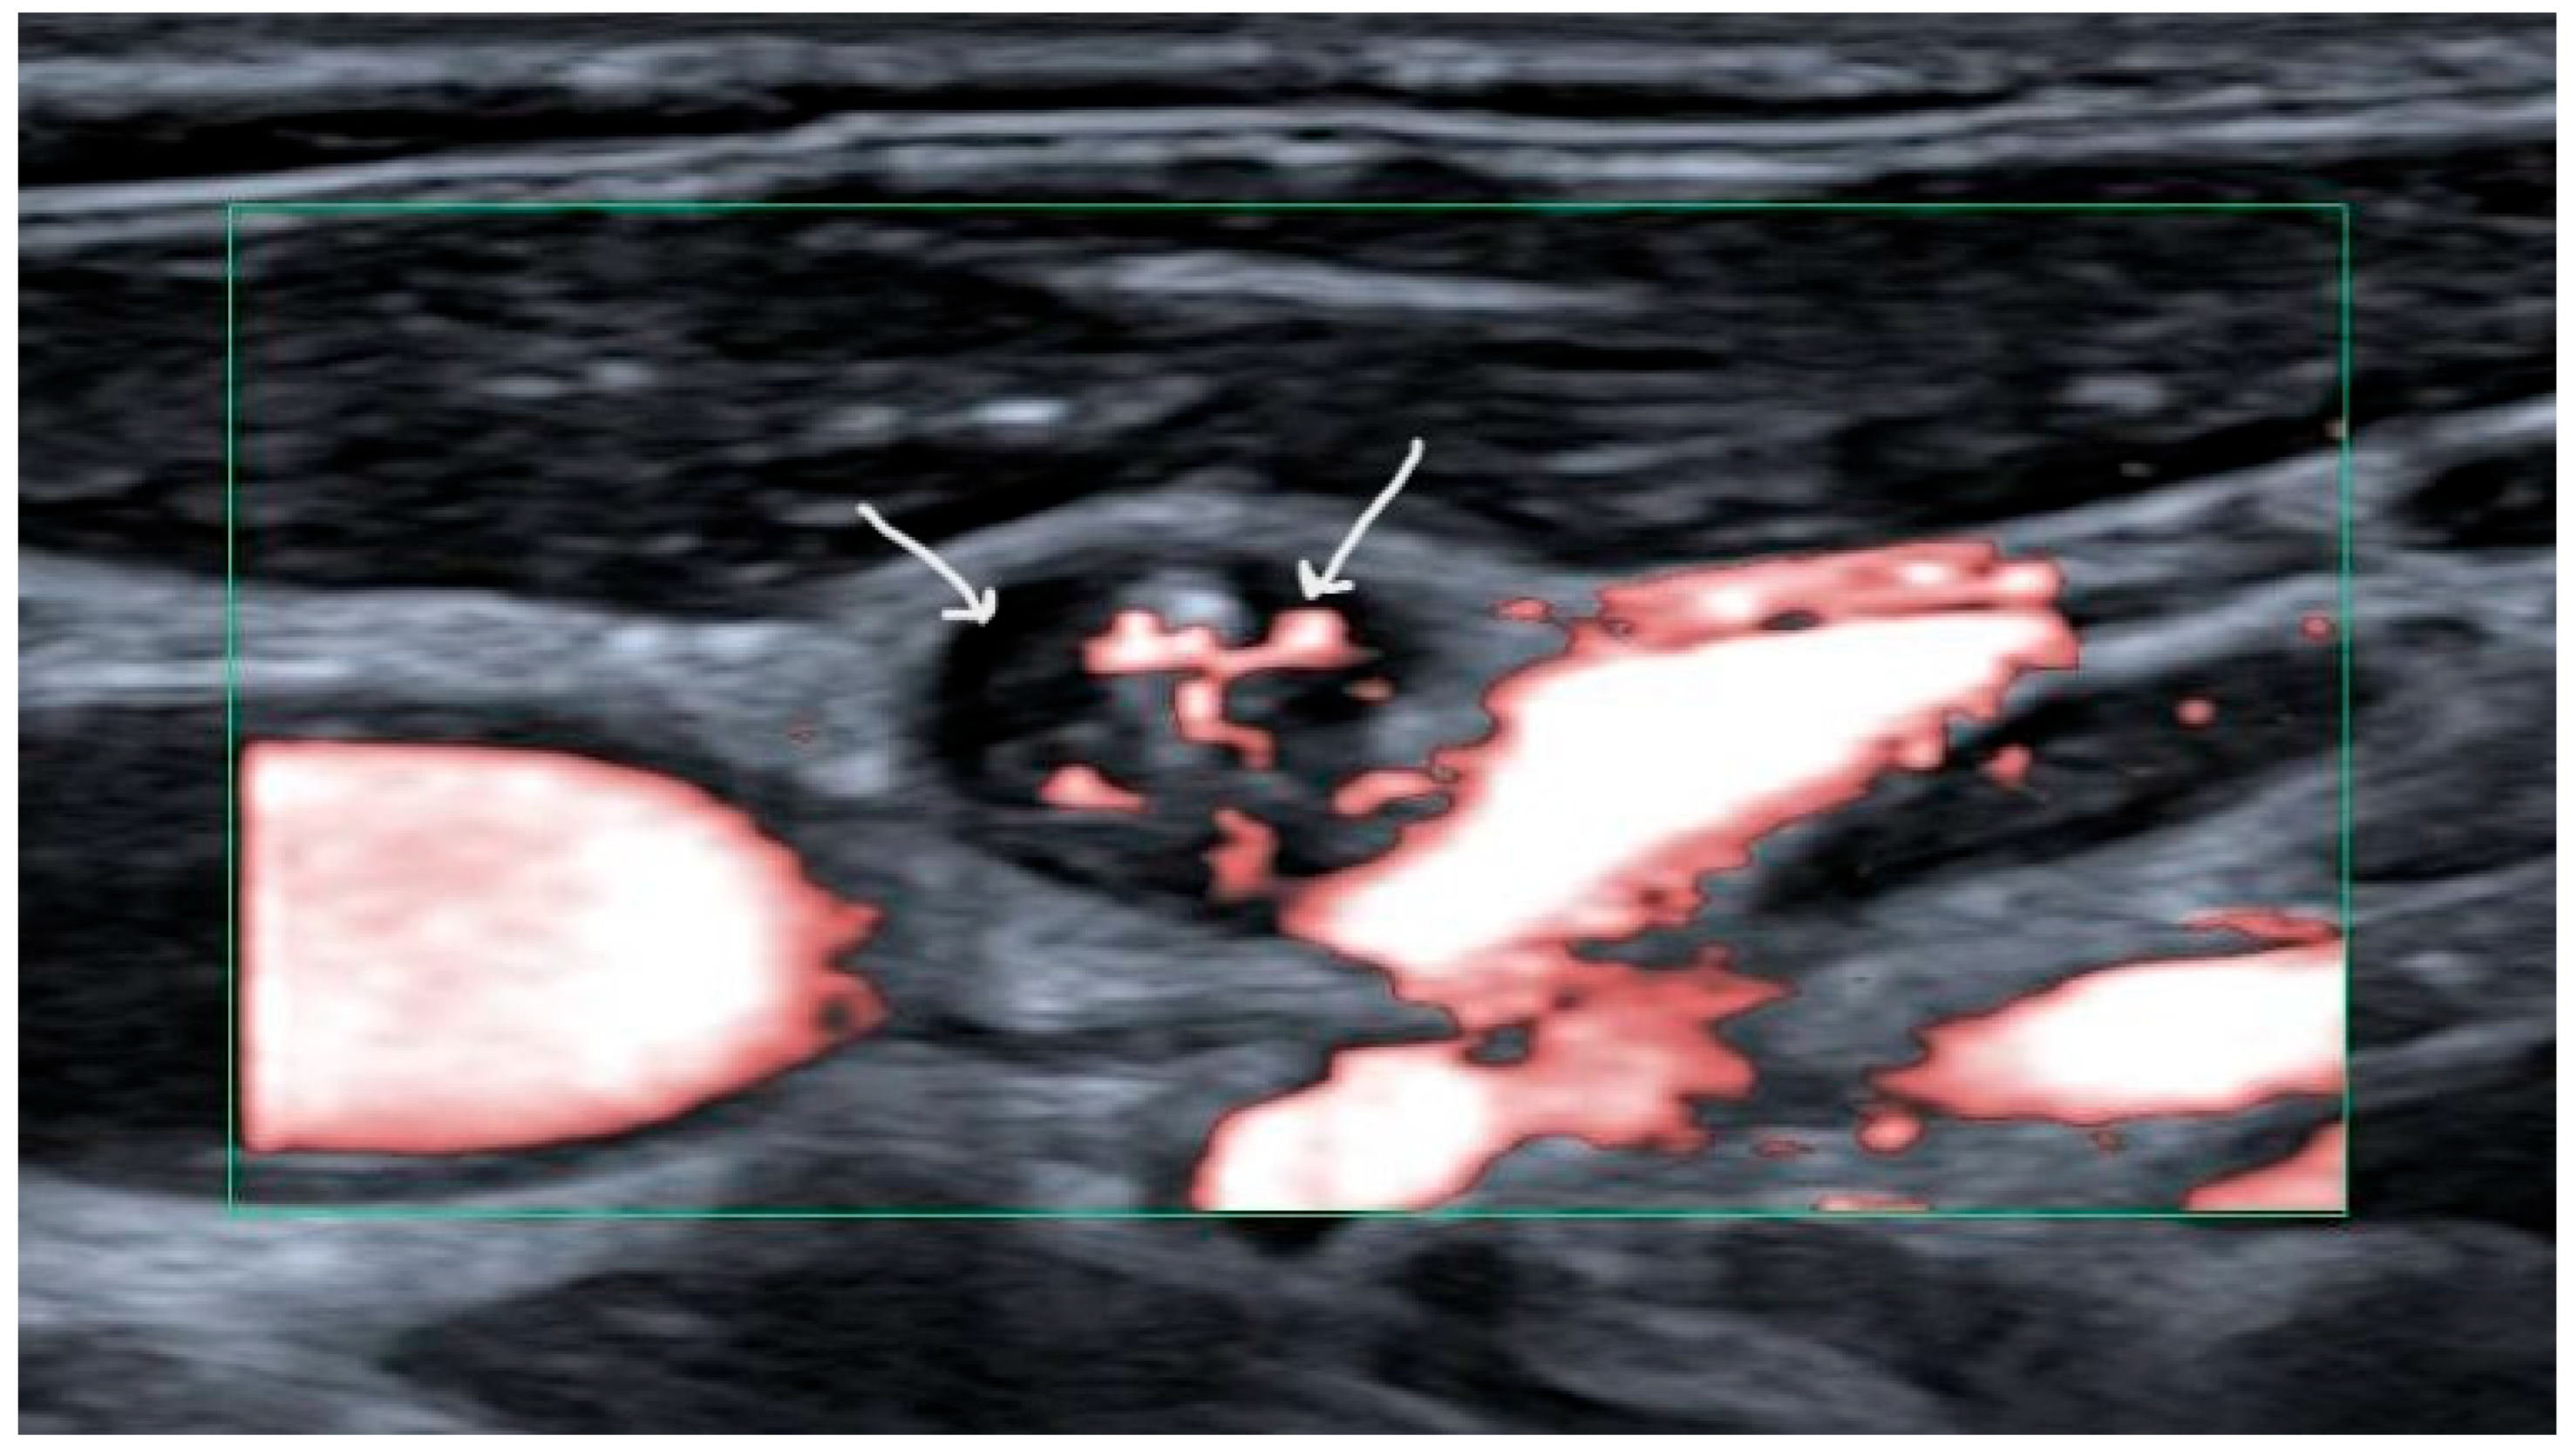

Preoperative ultrasound (US) of all neck levels is the recommended primary modality for work-up of papillary thyroid carcinoma [2]. Fine needle aspiration cytology (FNAC) should be performed for suspicious lymph nodes. Suspicious lymph nodes have been defined as harboring cystic areas, peripherally or diffusely increased vascularization, microcalcifications, and/or having a thyroid-like appearance (Figure 1) [9]. Thyroglobulin (Tg) titers should be measured in the needle washout fluid for increased sensitivity in papillary carcinoma [10]. When cytology and/or thyroglobulin levels in the needle washout fluid are in favor of lymph node metastases (LNM), in the setting of first-line therapy a therapeutic neck dissection is recommended [2].

Figure 1. Ultrasound image showing a suspicious lymph node with a cystic area (left arrow) and hypervascularization (right arrow).